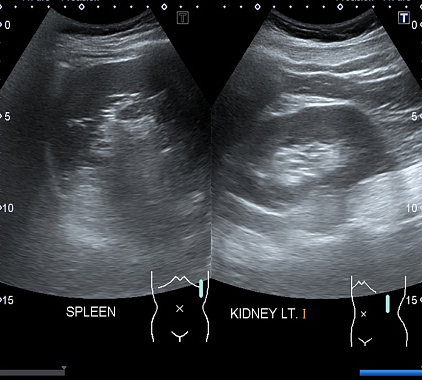

Фотогалерея

По окончании процедуры результат выдается практически сразу. В ходе расшифровки доктор анализирует снимки органа. Измеряет размеры. Определяет другие его особенности. Сравнивает с нормальными значениями. Врач отмечает присутствие и локализацию выявленных патологических процессов. Устанавливает их параметры, форму, протяженность, контуры, степень инвазии. Данные специалист переносит в протокол. Печатает самые информативные фотографии.

Норма размеров селезенки по УЗИ у взрослых:

- длина в промежутке от 8 до 14 сантиметров;

- ширина около 5–8 сантиметров;

- толщина – 3–5 сантиметров;

- вес у лиц женского пола примерно 152 грамма, у лиц мужского пола – 192–200 грамм;

- эхогенность органа средняя;

- структура однородная;

- патологические включения отсутствуют.